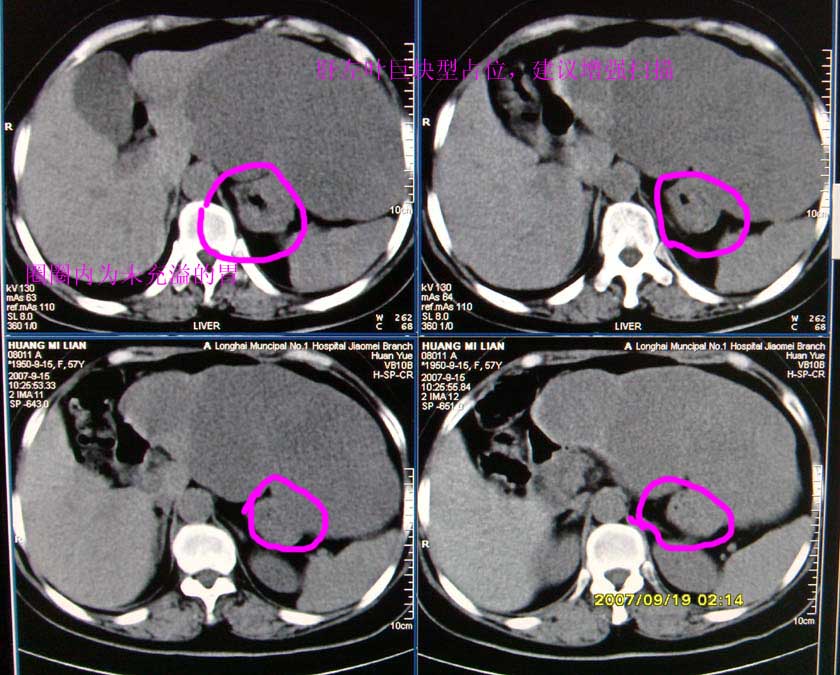

以下是引用逸风在2007-9-19 20:11:00的发言:[br]定位在肝左叶应该没有问题![br]ct显示肝左叶巨大低密度病灶,ct值30hu,密度欠均匀,里面似可见更低密度区;肝门及腹膜后未见明确肿大淋巴结.其与胃之间脂肪间隙存在;彩超提示病灶多发.[br]我个人觉得首先应该增强扫描,从平扫所见结合超声,首先应该考虑血管瘤.

以下是引用davisxuyong在2007-9-19 16:29:00的发言:[br]肝左叶大片状低密度灶,肝癌待排,建议增强。